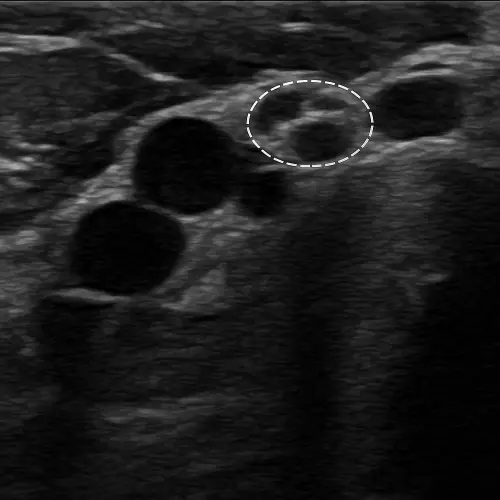

Ультразвуковое исследование периферических нервов — это метод ультразвуковой диагностики для оценки структурных изменений нервных волокон в режиме реального времени. Врач видит поперечное сечение нерва, его толщину, эхоструктуру, наличие отека или рубцовых изменений. В отличие от электронейромиографии, которая оценивает функцию нервов, УЗИ показывает их анатомию и структурные изменения.

Мы используем ультразвуковую систему Mindray Resona I8 на платформе ZST+. Это экспертное оборудование с высокочастотными линейными датчиками 12-18 МГц. Они позволяют визуализировать даже мелкие нервные ветви с высоким разрешением.

В работе применяем протоколы динамического сканирования с функциональными пробами. Врач может попросить вас согнуть или разогнуть конечность, чтобы увидеть, как нерв смещается при движениях и где происходит его ущемление. При необходимости используем режим эластографии для дополнительной оценки жесткости тканей вокруг нерва.